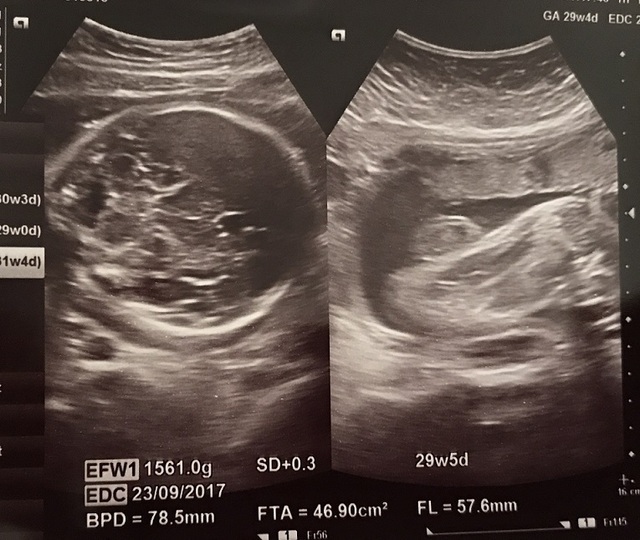

28週2日(28w2d)のエコー写真

28週2日(28w2d・男の子)かっぴー&コロ助 さん(33歳)

エコー写真撮影時のエピソード:

いつもエコーを撮る時、なかなか顔を見せてくれず、ほとんどが下半身ばかり(笑) でもこの時はドヤ顔を見せてくれて大笑いしました!

この頃は胎動も激しく毎日お腹をドカドカ蹴っ飛ばしてました!今でも脚の力は凄いです。 そんな息子も半年後にはお兄ちゃんに。